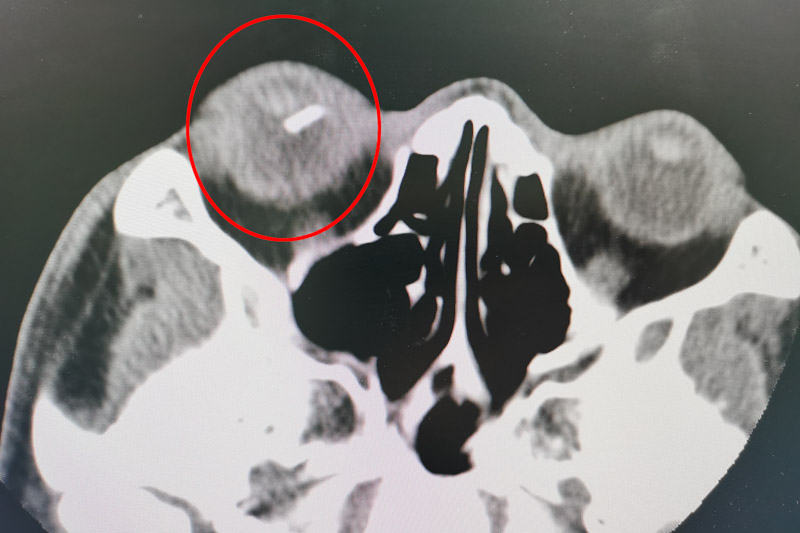

經檢查,發現患者右眼眼球已被穿通,眼球內還殘留有玻璃體異物,目前患者視物不清,只有光感,情況十分危急。眼科團隊針對該患者的情況立刻開展了術前討論,一致認為可以通過玻璃體切割術清除玻璃體內的積血及機化組織并摘除異物,保住患者的眼球及視力。

但該眼內手術難度很大,稍有不慎就可能出現眼內出血、眼內感染、玻璃片術中再次掉落損傷視網膜甚至黃斑部的風險。為確保手術萬無一失,眼科團隊做了詳細、周密的術前準備。術中使用微創23G玻璃體切割系統,在眼球上建立直徑為毫米級別的套管通道,使用顯微器械進行手術處理。通過顯微鏡可以看到視網膜上亮晶晶的玻璃碎片,玻璃碎片表面光滑,大小是手術切口的十倍左右。施術者小心翼翼從碎片兩側頭端、側面輕輕翻開嘗試夾取,稍有不慎,就會損傷視網膜,造成二次傷害。最終憑借高超的技巧,將長1.4cm的玻璃碎片成功取出,保住了患者的眼球。